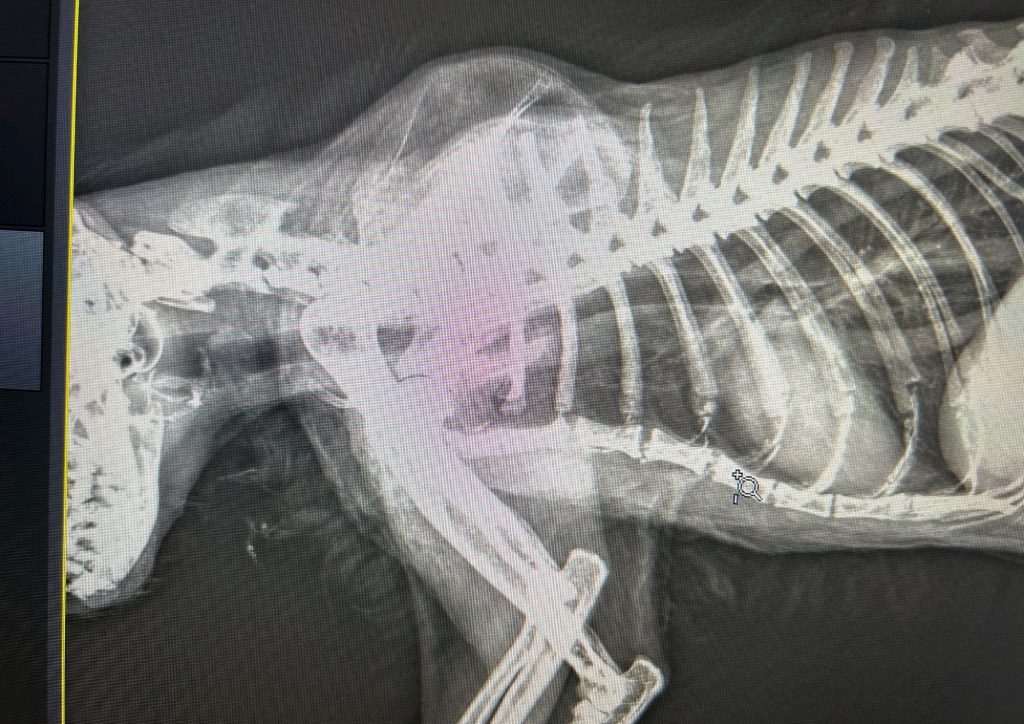

A x-ray reveals the scale of Taffy’s injury

The hospital identified that Taffy’s trachea had been “perforated with a pellet” and he was transferred to the PDSA in Hendon.

The PDSA said he had been shot between the neck and spine with a “suspected air rifle”, and advised that because he was so badly injured, Taffy was unlikely to pull through.